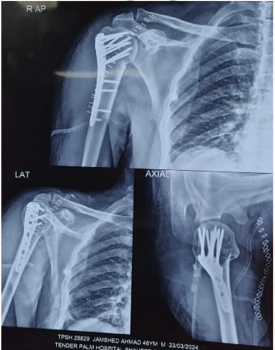

I specialised in all kinds of Knee and Shoulder surgery be it Joint Replacements or Joint Preservation, be it conventional technique Arthroscopic or Robotic